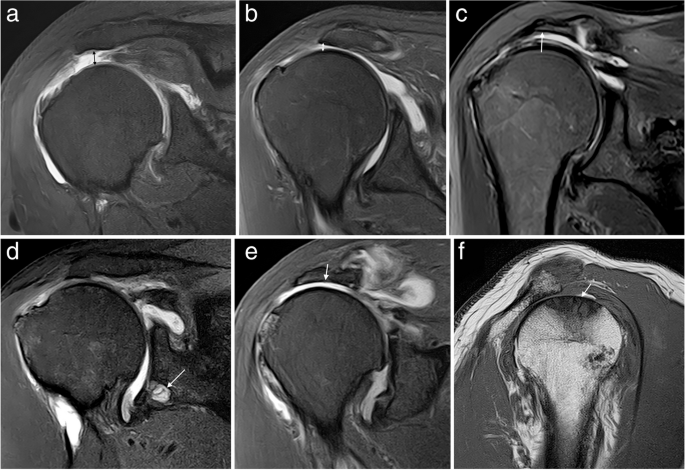

- Ecografie musculo-scheletală: rapidă, accesibilă, permite vizualizarea leziunilor tendinoase;

- RMN (rezonanță magnetică nucleară): standardul de aur pentru evaluarea detaliată a tendoanelor, mușchilor și structurilor periarticulare;